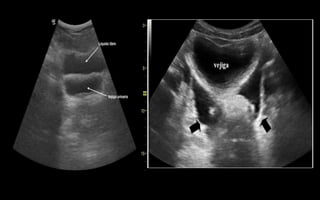

Sombra acústica posterior

• Zonas sin ecos que aparecen detrás de estructuras que reflejan todos los

ultrasonidos. La imagen ecográfica muestra una zona oscura detrás de una

estructura hiperecogénica. Es una interfase muy reflexiva y casi toda la

energía del haz sónico incidente sobre ellas se reflejará. Es similar a la

sombra que emite un edificio en un día soleado. Ejemplo fisiológico: el

hueso. Ejemplo patológico: cálculos o calcificaciones. La sombra sucia es

característica del gas dentro de los tejidos. La sombra por refracción o

sombra por ángulo crítico se observa cuando se visualizan objetos con

superficie curvada como la diáfisis de un hueso largo

Refuerzo acústico posterior

• Aumento en la amplitud de los ecos que se generan tras atravesar

una estructura anecoica. La imagen ecográfica muestra una

estructura anecoica e inmediatamente detrás de esta aparece una

zona hiperecogénica. Se da detrás de estructuras que contienen

líquido. Ejemplo fisiológico: la vesícula biliar, un vaso. Ejemplo

patológico: un quiste, un derrame